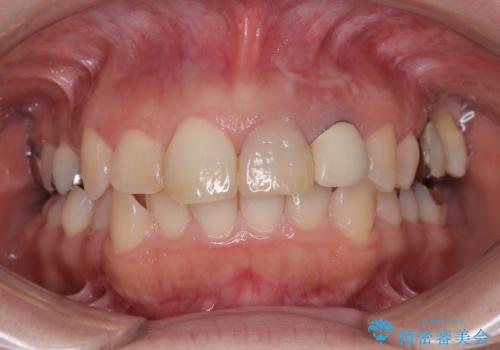

- 前歯2本の変色を気にして来院された患者様です。

2本とも歯の神経が取り除かれており、真ん中の歯は徐々に歯の色が茶色くなってきており、隣の歯は保険診療で装着したプラスチックのクラウンが徐々に黄ばんできている状態でした。

以前歯根端切除術を受けているものの、現在の主流とは異なる術式で行われているため、再度歯根端切除術を行うこととしました。

痛みが改善したことを確認した上で、オールセラミッククラウンにて補綴治療を行うこととしました。